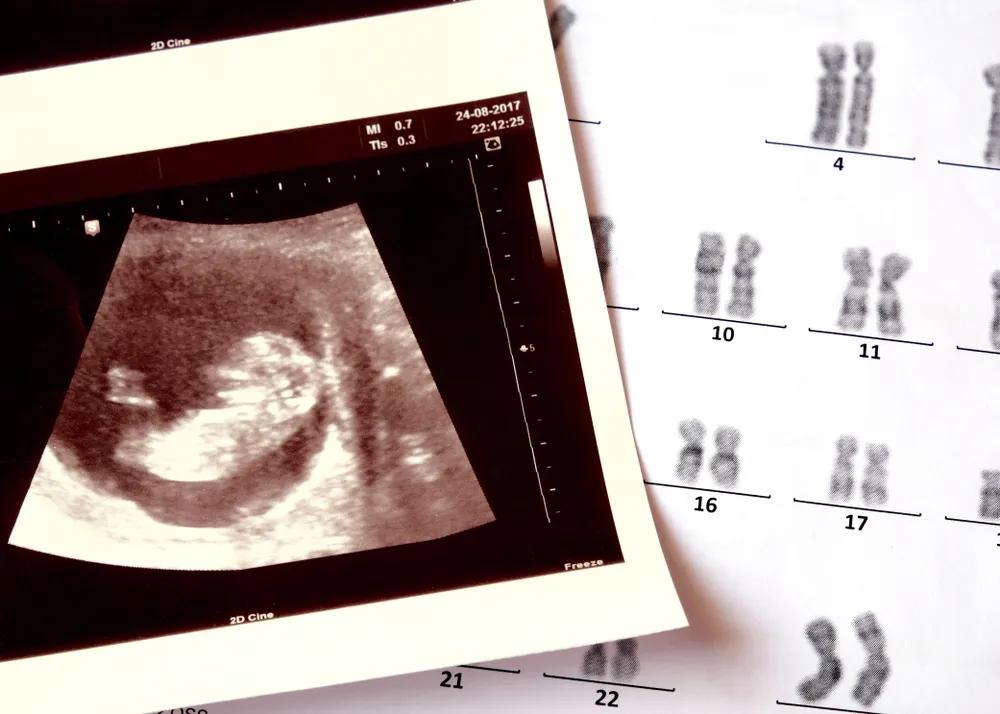

三天以后,医院会通知曾纪琪和丈夫,他们的卵子和精子有没有结合成受精卵。「像学生查成绩一样的,医生会告诉你,现在取了多少个卵泡,培育成多少个受精卵,质量怎么样,是 A 级还是 B 级,是移植,还是直接冷冻。」

图源:站酷海洛